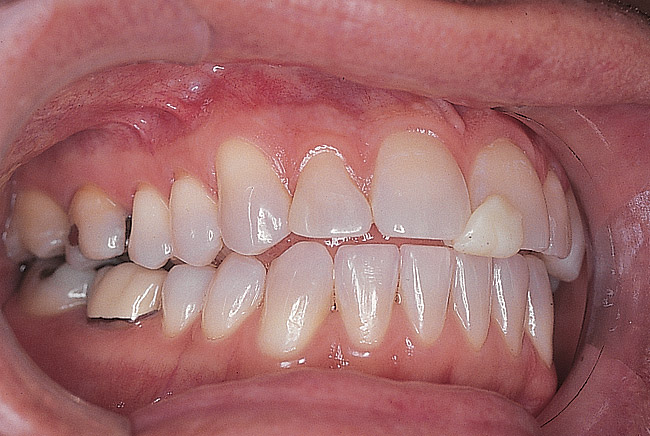

Figure 1  Preoperative facial view demonstrating maximum tooth display.

Figure 1